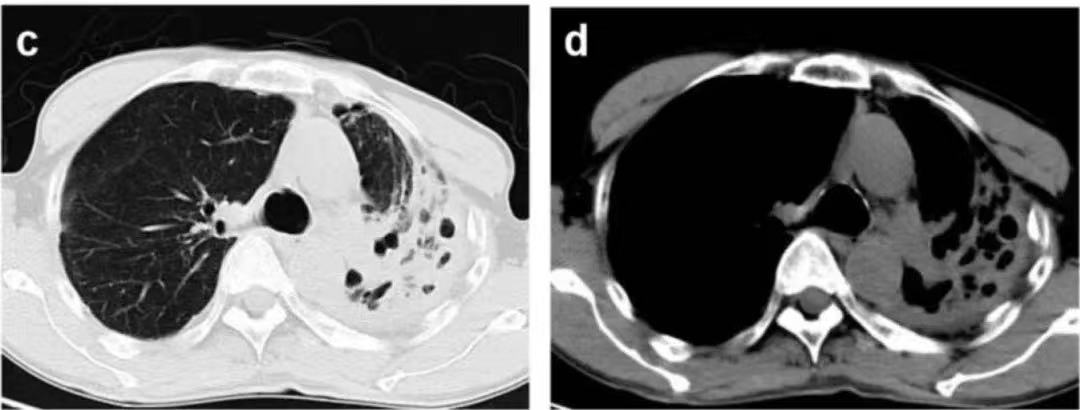

ÐØ²¿CTÏÔʾ×ó·ÎÉÏÒ¶ÓÐÂýÐÔѬȾºÍÊÜËð²¡Ôî